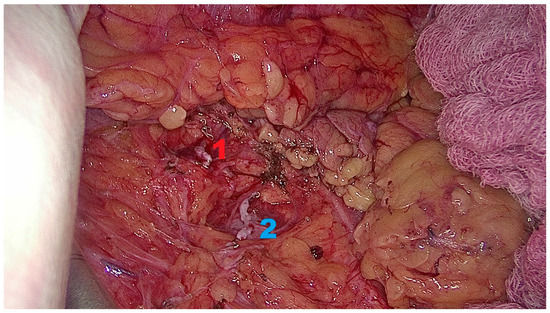

Background: Minimally invasive techniques for living donor nephrectomy are crucial for donor safety and promoting organ donation. Hand-Assisted Retroperitoneoscopic Donor Nephrectomy (HARP-DN) combines the benefits of minimally invasive surgery with...